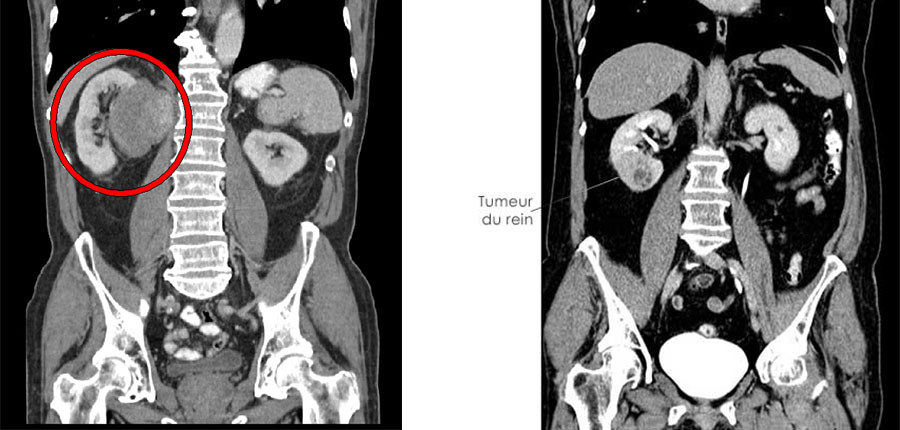

Sept fois sur dix, la découverte est fortuite, à l’occasion d’une imagerie abdominale, par scanner ou IRM, prescrite pour une autre raison médicale.

Dans l’objectif de diagnostiquer un cancer du rein, le médecin traitant demande un bilan radiologique et biologique.

Le but recherché est de déterminer si le cancer est localisé au rein ou non, c’est à dire étendu en périphérie immédiate de celui-ci (graisse qui l’entoure, veine rénale ou veine cave) ou déjà métastasé à distance du rein touchant ganglions, poumon, os et foie.

Le bilan radiologique, explique Dr Bounhir BOUMEHDI, radiologue à Salé, un scanner thoraco-abdominal avec injection d’un produit de contraste dans les vaisseaux. Parfois une IRM est demandée pour préciser le degré d’extension à une veine cave ou quand le scanner est contre-indiqué, par exemple, chez un patient qui souffre d’une insuffisance rénale.

L’imagerie (les examens radiologiques) suffit à guider la stratégie thérapeutique, précise Pr Mohammed AMER, urologue à l’hôpital militaire de Rabat.